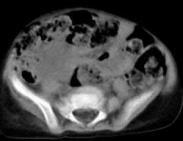

先天性膽總管囊腫又稱膽總管擴張癥,是以膽總管囊腫或梭狀擴張,伴有或不伴有肝內膽管擴張為特點的膽道畸形,是最常見的一種先天性異常,也為先天性肝膽系統囊腫中最多見的一種疾病,可同時存在其他病變。一般認為亞洲人群中的發病率明顯高于歐美,多在嬰兒和兒童期發現。女性發病高于男性,占總發病率的60%~80%。